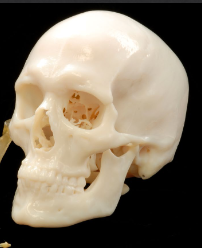

3D Imaging

A technology that creates three-dimensional representations of dental and facial structures.

3D Visualization

The ability to view anatomy in three dimensions, improving accuracy in diagnosis and treatment planning.

Segmentation

The process of separating distinct structures in an image for analysis and treatment planning.

segmenting the CBCT imaging

3d modeling of bone used for planning